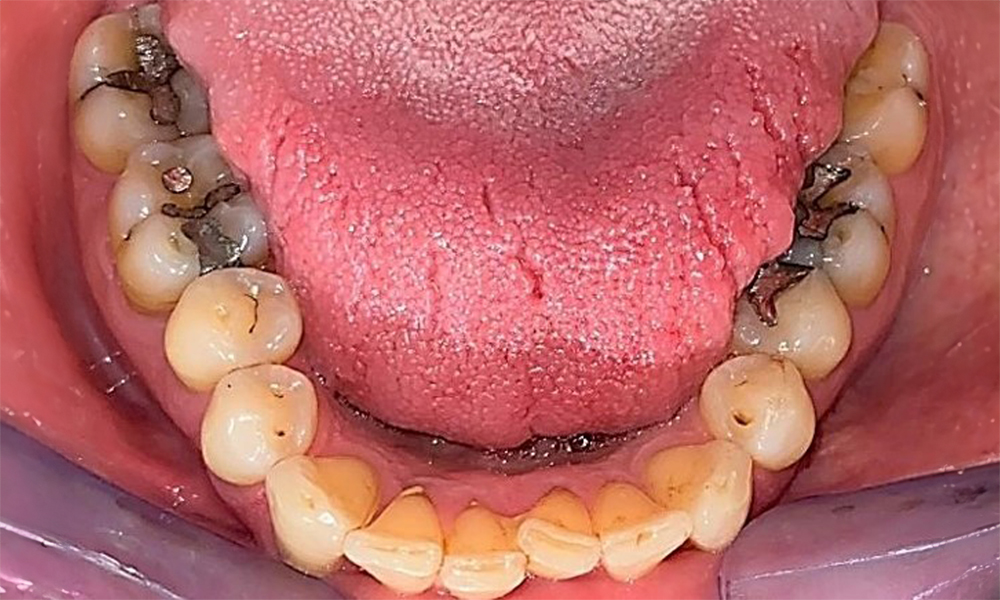

Pacientul prezintă dentiție completă cu 28 de dinți, care include obturații din amalgam și compozit pe molari și premolari. Există un spațiu marginal clinic vizibil la 14. Molarul 27 prezintă un inlay din aur adecvat. Se observă, de asemenea, atriții și abrazii generalizate. (Fig. 2, Fig. 3, Fig. 4, Fig. 5, Fig. 6)

Pacientul prezintă boală parodontală în stadiul II, gradul B (5). Profunzimile clinice de sondare observate, între 1 și 3 mm, se încadrează în limitele fiziologice. Localizat, s-au observat profunzimi de 5 mm, la nivel meziopalatin, atât pe 17, cât și pe 27. Se constată recesiuni generalizate de 1-3 mm, cu pierderi parțiale ale papilelor interdentare (Fig. 2, Fig. 3, Fig. 4)

Pacientul folosește periuțe interdentare și o periuță de dinți electrică. Aceasta demonstrează respectarea indicațiilor de întreținere și o bună înțelegere a igienei intraorale la domiciliu. Motivarea și reinstruirea regulată sunt indispensabile, datorită riscului de progresie a patologiei dentare, în special în ceea ce privește curățarea zonelor interdentare, aici fiind detectate adâncimi de sondare crescute. Se observă tartru localizat și o ușoară placă dentară în regiunea linguală a mandibulei anterioare, aceste aspecte vor fi indicate pacientului. Este posibil să fie necesară verificarea și adaptarea dimensiunii periuțelor interdentare. Se recomandă folosirea periuțelor cu peri moi, având în vedere prezența suprafețelor radiculare expuse, pentru prevenirea leziunilor cuneiforme. Se va utiliza pastă de dinți cu o valoare abrazivă scăzută.